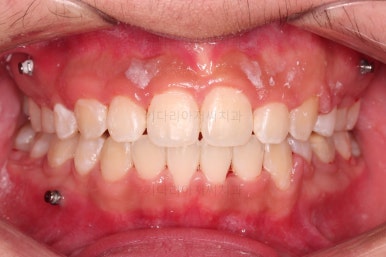

종료 시의 사진들을 전후 비교해 보겠습니다.

입매가 좋아졌고 입을 다무는 편안함도 좋아졌으며 치열이 가지런해졌으며 웃을 때 보이는 치열의 느낌도 좋고 교합도 잘 마무리 되었네요.

지켜봐도 되는 충치는 지켜보기로 여지를 남기고 필요한 충치치료도 마무리를 했습니다.

이상 부산청소년치아교정 키다리아저씨치과에서 시행한 덧니, 돌출입 개선 사례였습니다.